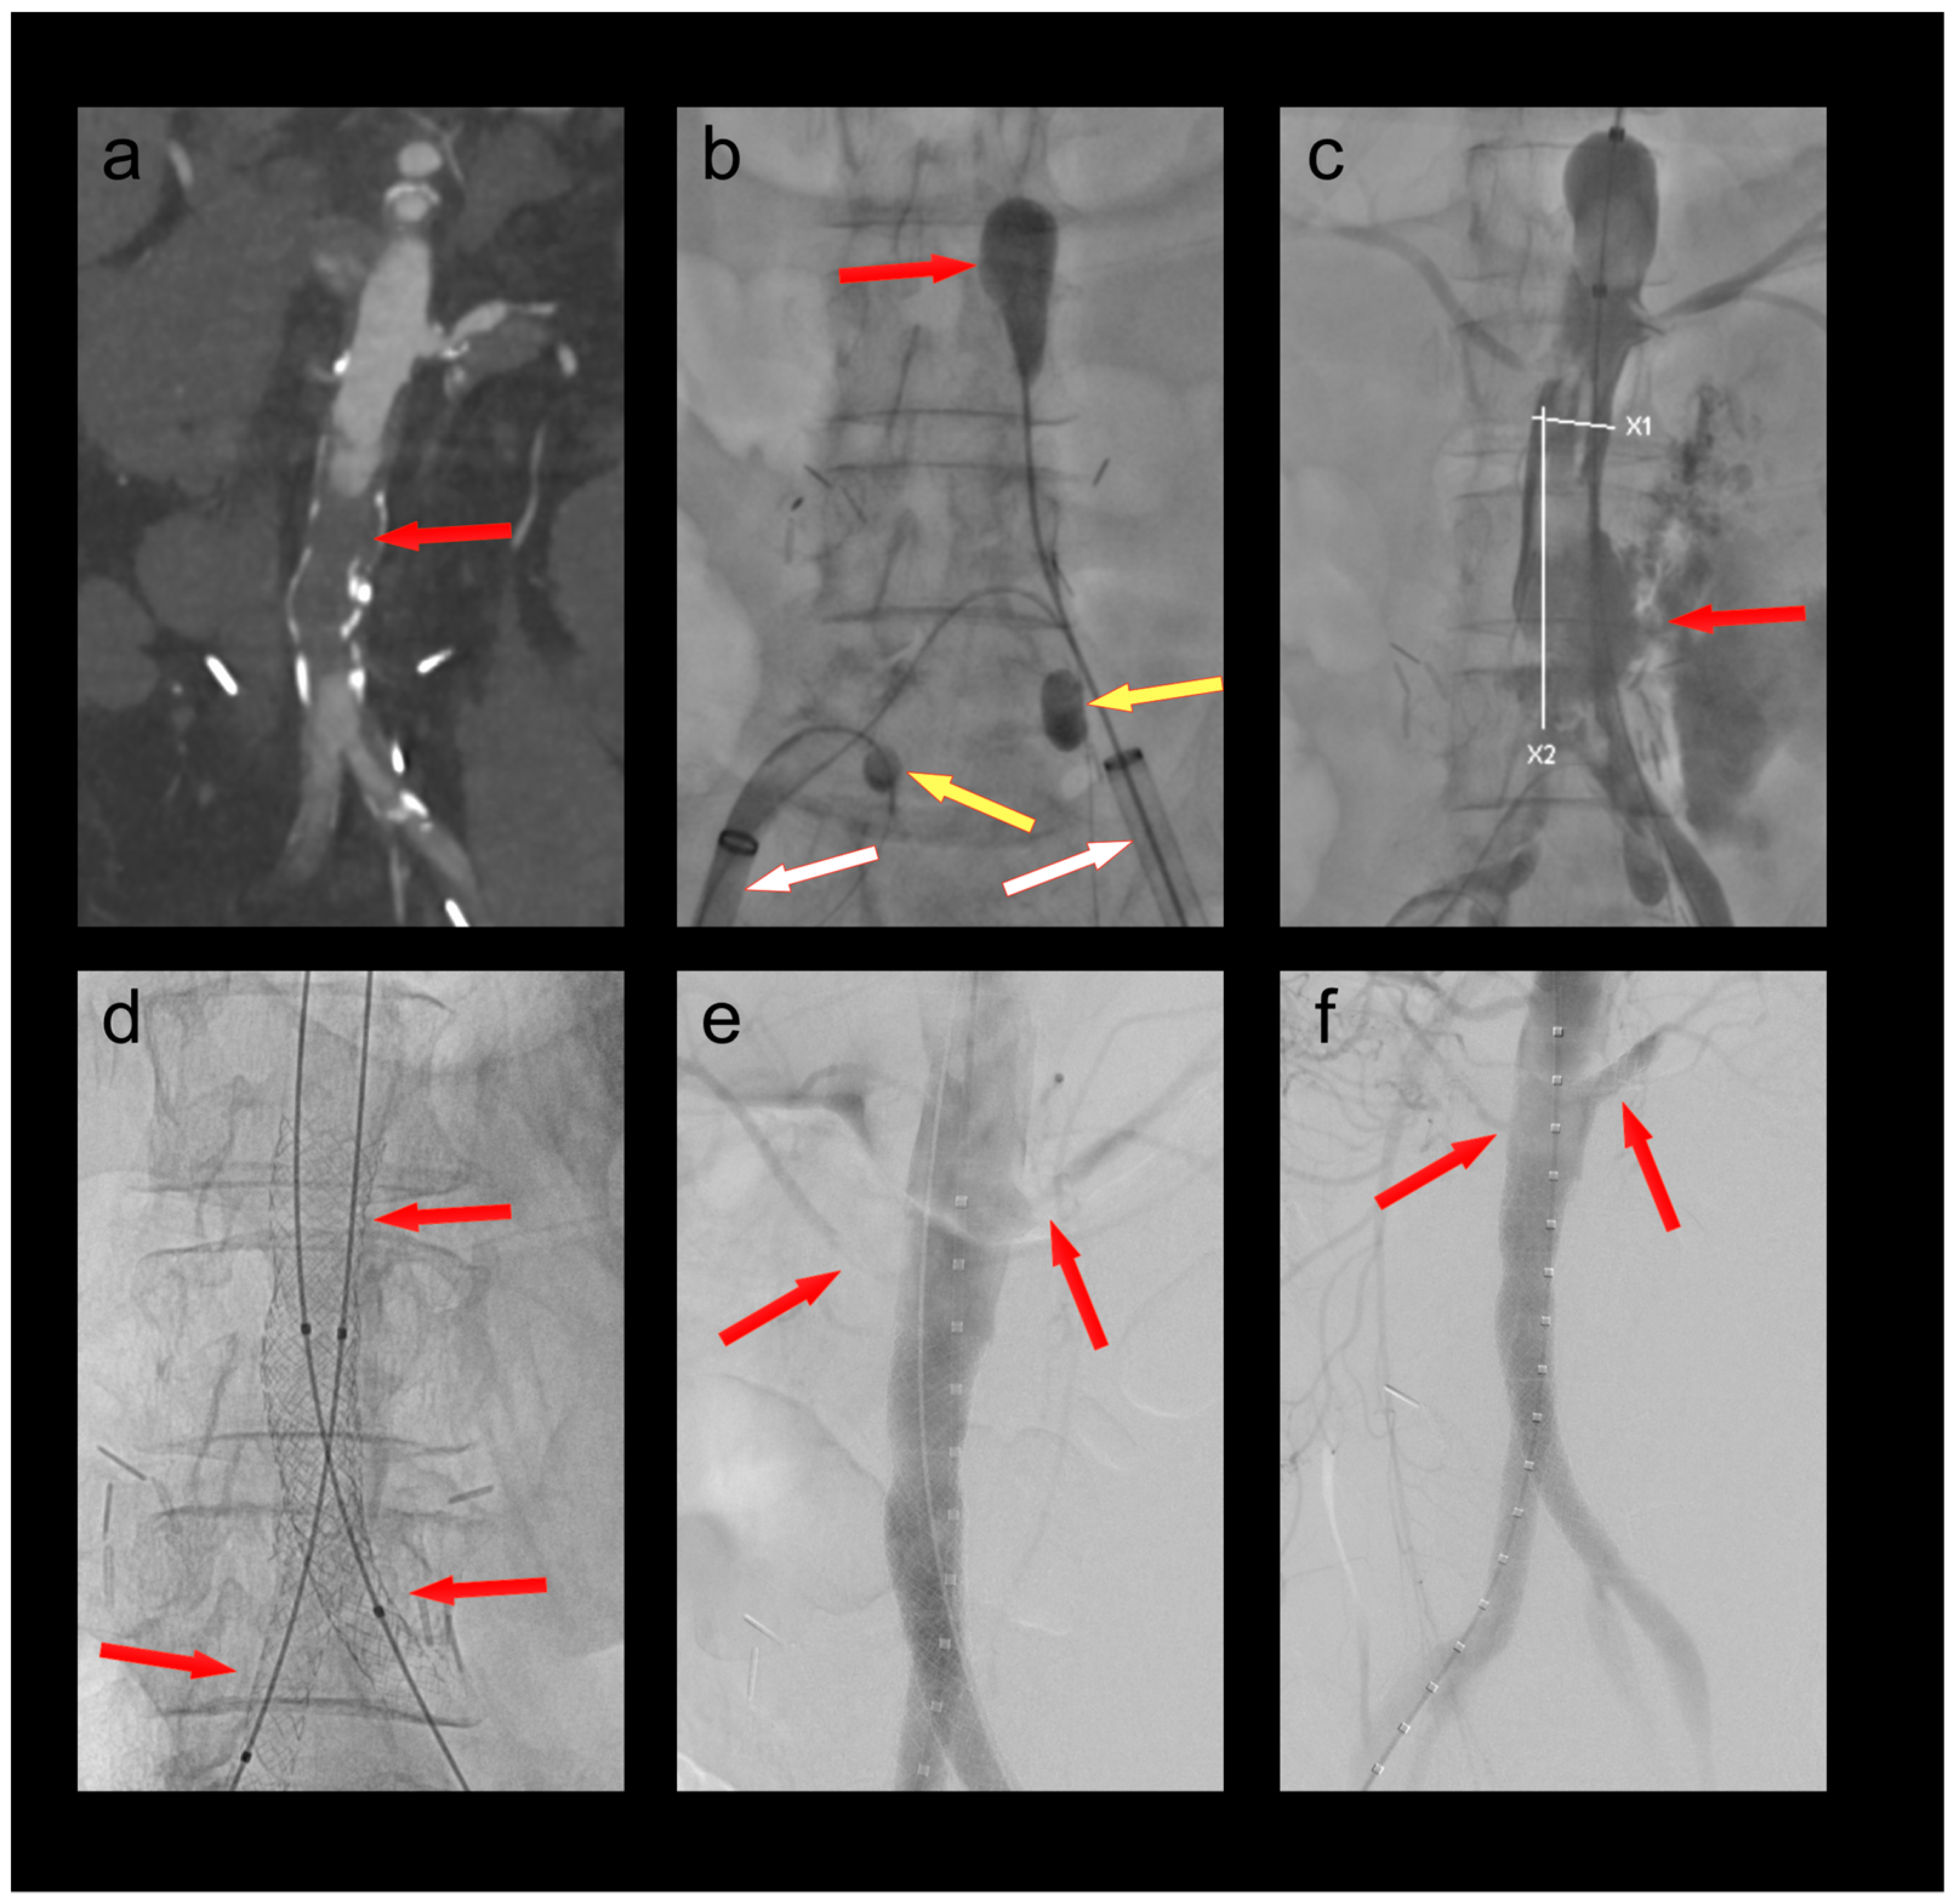

3.2. Patient 2

A 61-year-old female patient was admitted because of respiratory failure due to bilateral COVID-19 pneumonia. A CT angiography detected several appositional thrombi throughout the thoracoabdominal aorta, the biggest of which was located at the origin of the coeliac trunk (Figure 2). Another scan two days later showed progression of the thrombi in spite of therapeutic heparin. The coeliac trunk was nearly occluded, and the right hepatic artery was completely occluded. Furthermore, the patient had acute cholecystitis. To avoid further embolization, we decided to thrombectomize the aorta and the origin of the coeliac trunk. The coeliac trunk, superior mesenteric artery, and both renal arteries were protected by OTW Fogarty® catheters, while the hypogastric arteries were protected by advancing the large-bore sheaths into the common iliac arteries. Thrombectomy of the entire aorta into the large sheaths was performed using an 8–22F Fogarty® occlusion catheter (Figure 2). The 5.5F Fogarty catheter that blocked the coeliac trunk was then used to thrombectomize its origin. There was no relevant residual thrombus in the aorta or the coeliac trunk on completion angiography (Figure 2). No further thrombotic complications were seen under therapeutic anticoagulation, and the patient was discharged home after several months in the hospital.

Figure 2. (a) Thrombus in the aorta and in the origin of the coeliac trunk (red arrow); (b) thrombectomy (red arrow) of the thoracoabdominal aorta under balloon protection of the coeliac trunk, superior mesenteric artery, and both renal arteries (yellow arrows). The large-bore sheaths are occlusive in both common iliac arteries (white arrows); (c) Postoperative CT scan with no residual thrombus in the aorta or the coeliac trunk (red arrow).